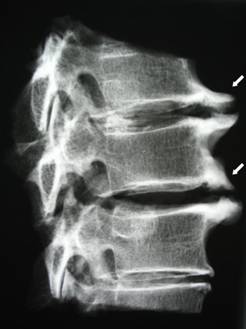

Клювовидные остеофиты

Главная причина образования клювовидных остеофитов в позвоночнике — прогрессирование спондилеза. Патологические наросты локализуются в передней области позвонков.

Из-за неравномерной продолговатой формы в виде скоб (по передним контурам th8 th9) при первичной диагностике врач может подумать, что это рак.

Избавиться от клювовидных наростов позвоночника можно с помощью хирургического вмешательства или терапии лекарствами. Неплохие результаты показывает физиотерапевтическое лечение.